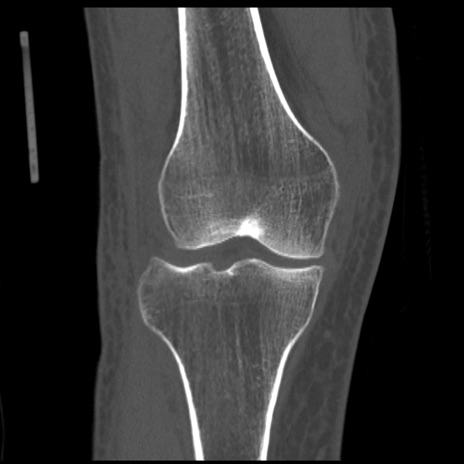

症例28 右膝関節CT(冠状断像)

右膝関節CT